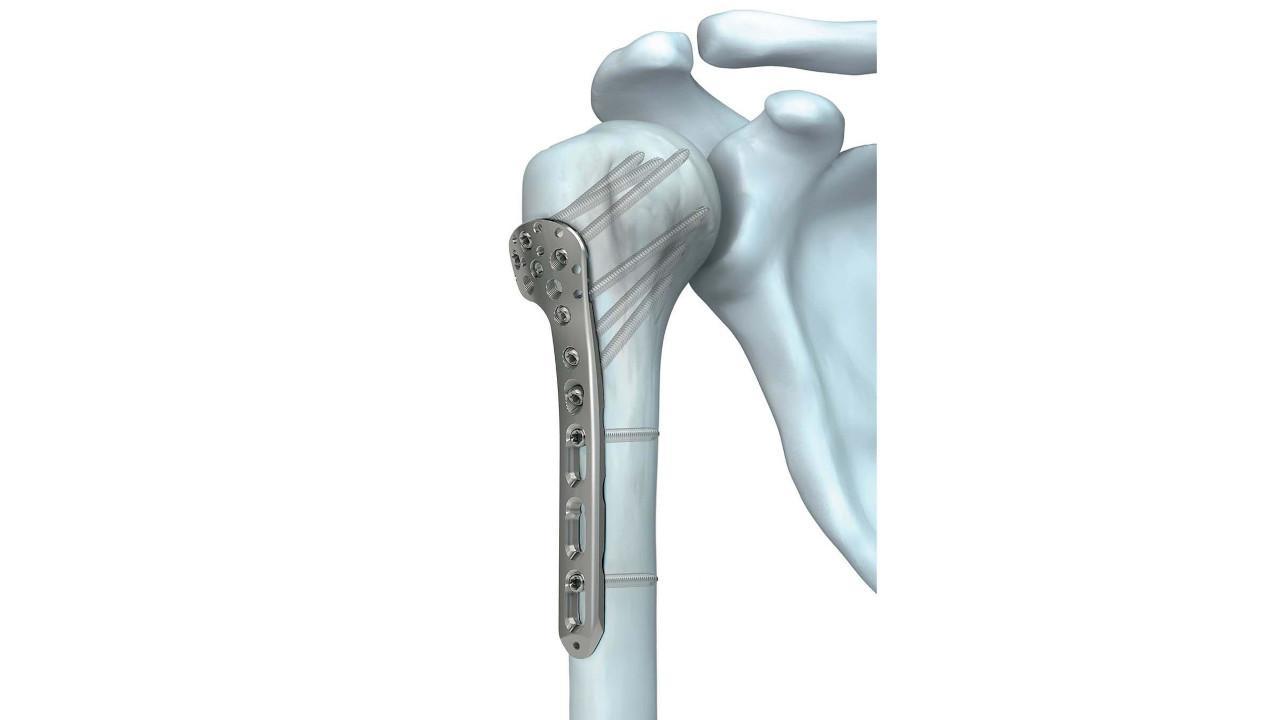

"I had my shoulder operated at Atulya Hospital by Dr. Raghav sir. His

treatment, behavior, and guidance were excellent. My recovery is also going very

smoothly. Thank you, Dr. Raghav sir!"